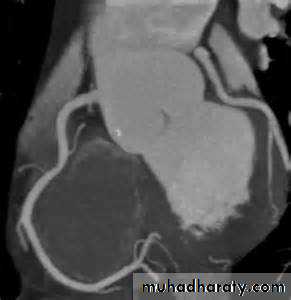

Computed Tomographic Imaging

Useful for imaging the cardiac chambers, great vessels , pericardium, and mediastinal structures and massesAnd recently even the coronaries (CT coronary angiography).